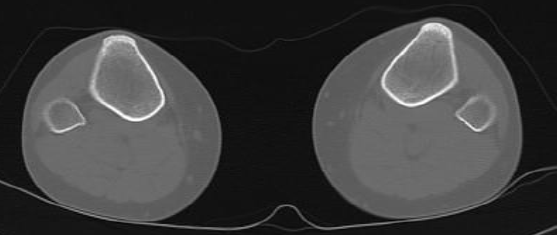

Coupes

D

Plateaux tibiaux

E

TTA

F

Malléoles tibiales